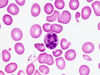

Which condition do hypersegmented neutrophils tend to be present in?

Megaloblastic anaemia